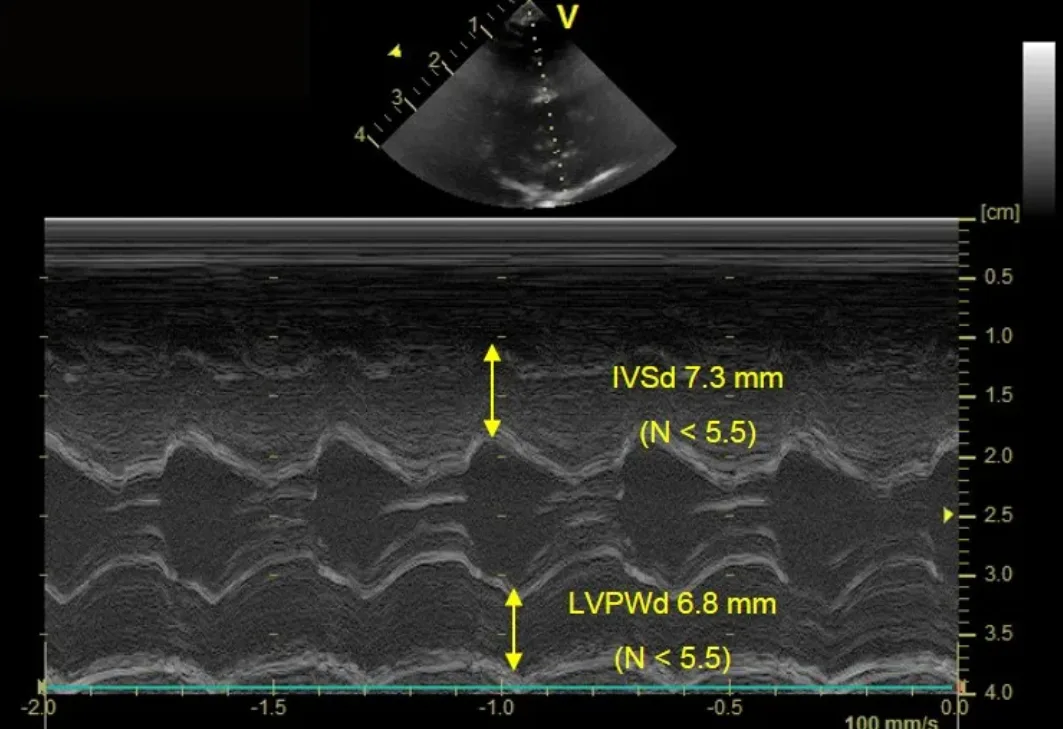

Stage B2 HCM

A clinically normal 3-year-old ragdoll cat with a loud murmur located at the left sternal border that demonstrates left ventricular hypertrophy (thickening) and left atrial dilation based on 2-dimensional echocardiographic evaluation. Figure 6A shows moderate-to-severe hypertrophy of the interventricular septum (IVSd 7.3 mm) and left ventricular posterior wall during diastole (LVPWd 6.8 mm).

IVSd = interventricular septum in diastole, LVPWd = left ventricular posterior wall in diastole